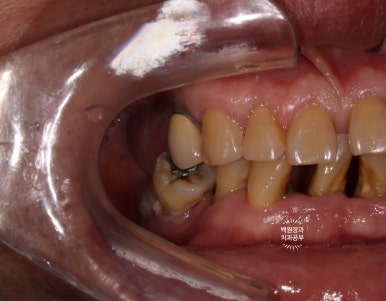

정면에서 찍어본 구강 내 사진 소견입니다.

다수의 치은연상치석, 치은연하치석이 침착되어 있고, 만성치주염으로 인해 치아가 제 위치를 상실하여,

치아의 병적이동 (pathologic migration)을 하고 있는 중이었죠.

풍치가 심해서 만성치주염을 오래 앓으신 분들은 치아 사이가 벌어져 심미적으로 불리한 모습을 많이 보이십니다.

게다가, 어금니들도 씹는 면끼리 물리지 못해서 이제 식사도 어려우신 상황이었어요.